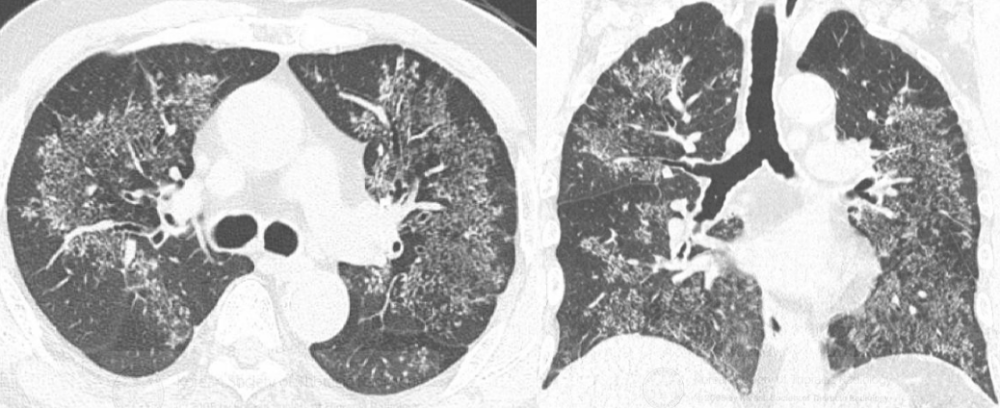

哮喘病人,影像上存在主要为外周分布的双肺实变,即可考虑慢性嗜酸性

外周为实变影,这主要是机化性肺炎的病人